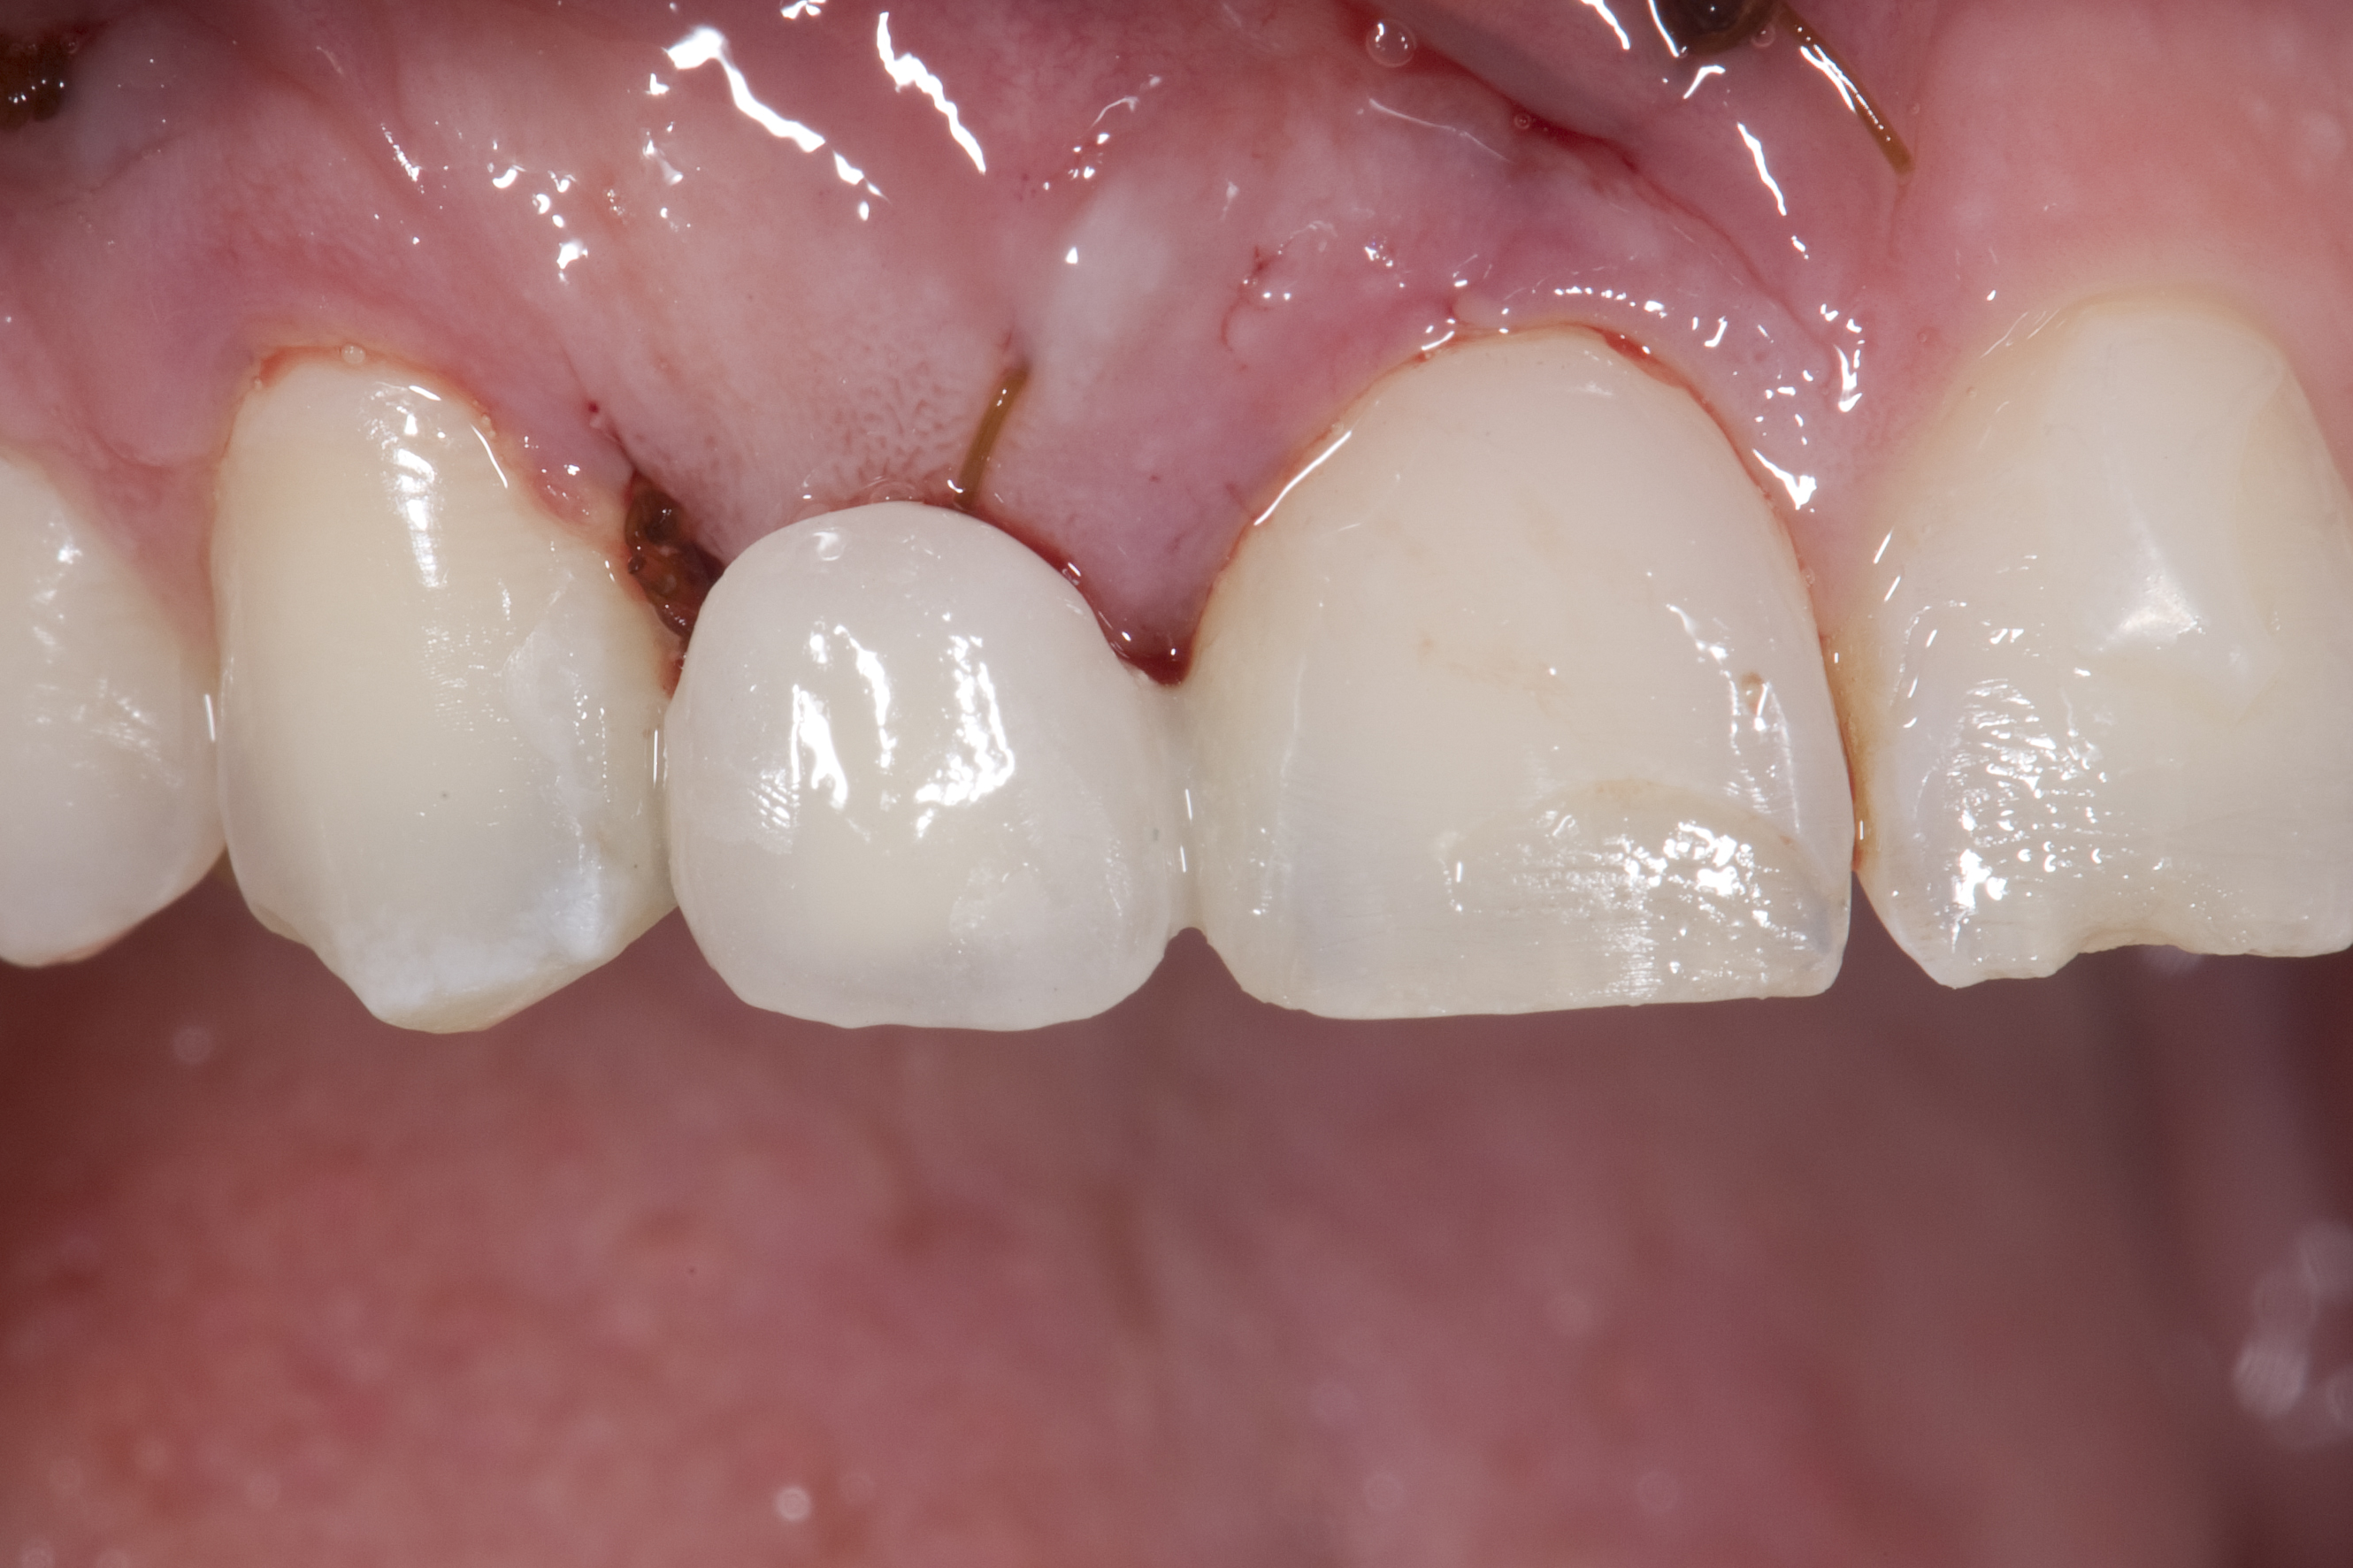

A 14-year-old patient presented to the office with his mother (Figure 1). His chief complaint involved the large spaces between the teeth created by his missing right maxillary lateral incisor and his small left maxillary lateral incisor. He desired to replace the missing tooth with an implant and create a beautiful smile. Upon examination, he was found to have a class I canine and molar relationship, but because he had a tooth size/arch size discrepancy and space distal to the right central incisor, the remaining incisors had drifted to the right. The left maxillary lateral incisor was peg-shaped and in a cross bite position. Studies have shown a clear association between congenitally missing teeth and reduced tooth size.59-62 Because he was only 14-years-old at the time and could not have implants placed until the cessation of growth (somewhere in the vicinity of 22 years old), he was sent to the orthodontist for alignment of the teeth.16,17 After 2 years of orthodontics, the appliances were removed, and his tooth coloration was improved using carbamide peroxide bleaching (Figure 2). Because some form of provisional needed to be placed until he was finished growing, a double-wing metal resin-bonded bridge was chosen. As discussed earlier, this is the ideal transitional prosthesis for patients that have congenitally missing maxillary lateral incisors. The benefits of this type of prosthesis include its ability to be removed and rebonded during the surgical phase of treatment and its ability to retain the roots in their proper position after orthodontic treatment.16 The final plan for the patient was to increase the width of the central and the maxillary left lateral incisor, utilizing porcelain laminate veneers to achieve the appropriate width/length ratio of 80%. A wax-up was created to idealize tooth size, a putty matrix was made from the wax-up to facilitate bonding of the incisors, and a non-precious, double-wing metal resin-bonded bridge was fabricated for lateral incisor replacement. Once the teeth were bonded to ideal size, the “Maryland Bridge” was fabricated from a polyvinyl arch impression with the newly bonded teeth (Figure 3). The metal frame was cast from a non-precious alloy to allow for fabrication of a very thin frame and to create a better surface for bonding. After sandblasting the internal aspect of the frame with CoJet™ silica (3M ESPE), accomplishing salinization, and executing cementation with a dual-cure resin cement, a fairly good adhesion to the frame was anticipated.29 The enamel surface was etched with phosphoric acid for 30 seconds, the primer (Single Bond Plus, 3M ESPE) was applied to both the internal surface of the sandblasted framework and the etched enamel, and the bridge was cemented with RelyX™ ARC (3M Espe) dual-cured resin cement (Figure 4 and Figure 5).

(1.) Initial presentation. Note midline shift to right, missing right lateral incisor, and diminutive left lateral incisor in crossbite.

Figure 1

(2.) After orthodontic alignment of teeth and bleaching. Note alveolar deficiency in right lateral incisor site and diminutive left lateral incisor.

Figure 2